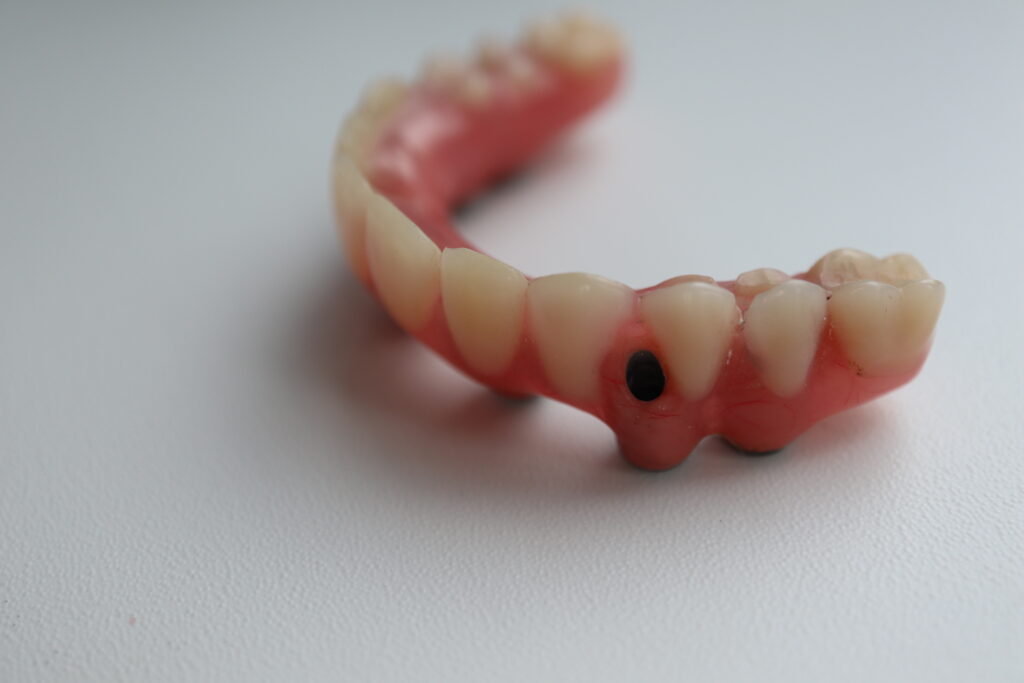

Что было сделано:

На верхней челюсти были удалены зубы и проведена комплексная имплантация по системе All-on-6,

установлены 6 имплантатов Megagen AnyOne.

Спустя 7 дней на верхней челюсти зафиксирован металлоакриловый протез из 12 зубов.